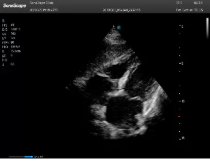

左室長軸

劍下四腔

四腔心